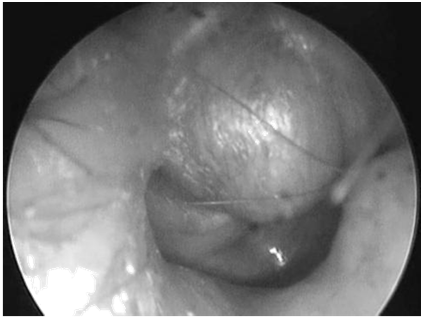

In October 2010, a 48-year old man presented at our otorhinolaryngology department with a 3-month history of right hearing loss, tinnitus and aural fullness. The otoscopy revealed a gray-white nonpulsatile poster superior retro tympanic mass with intact tympanic membrane (Figure 1). The hearing test confirmed a mild conductive hearing loss. A high-resolution temporal CT showed a well-circumscribed soft-tissue mass in the epitympanic area that was embedded in the ossicles without evidence of bone erosion (Figure 2). MRI revealed a middle ear mass with low intensity on T1weighted images, high intensity on T2-weighted images, and enhancement after administration of gadolinium.

Figure 1 Otoscopy: Right ear. Posterosuperior retrotympanic mass.